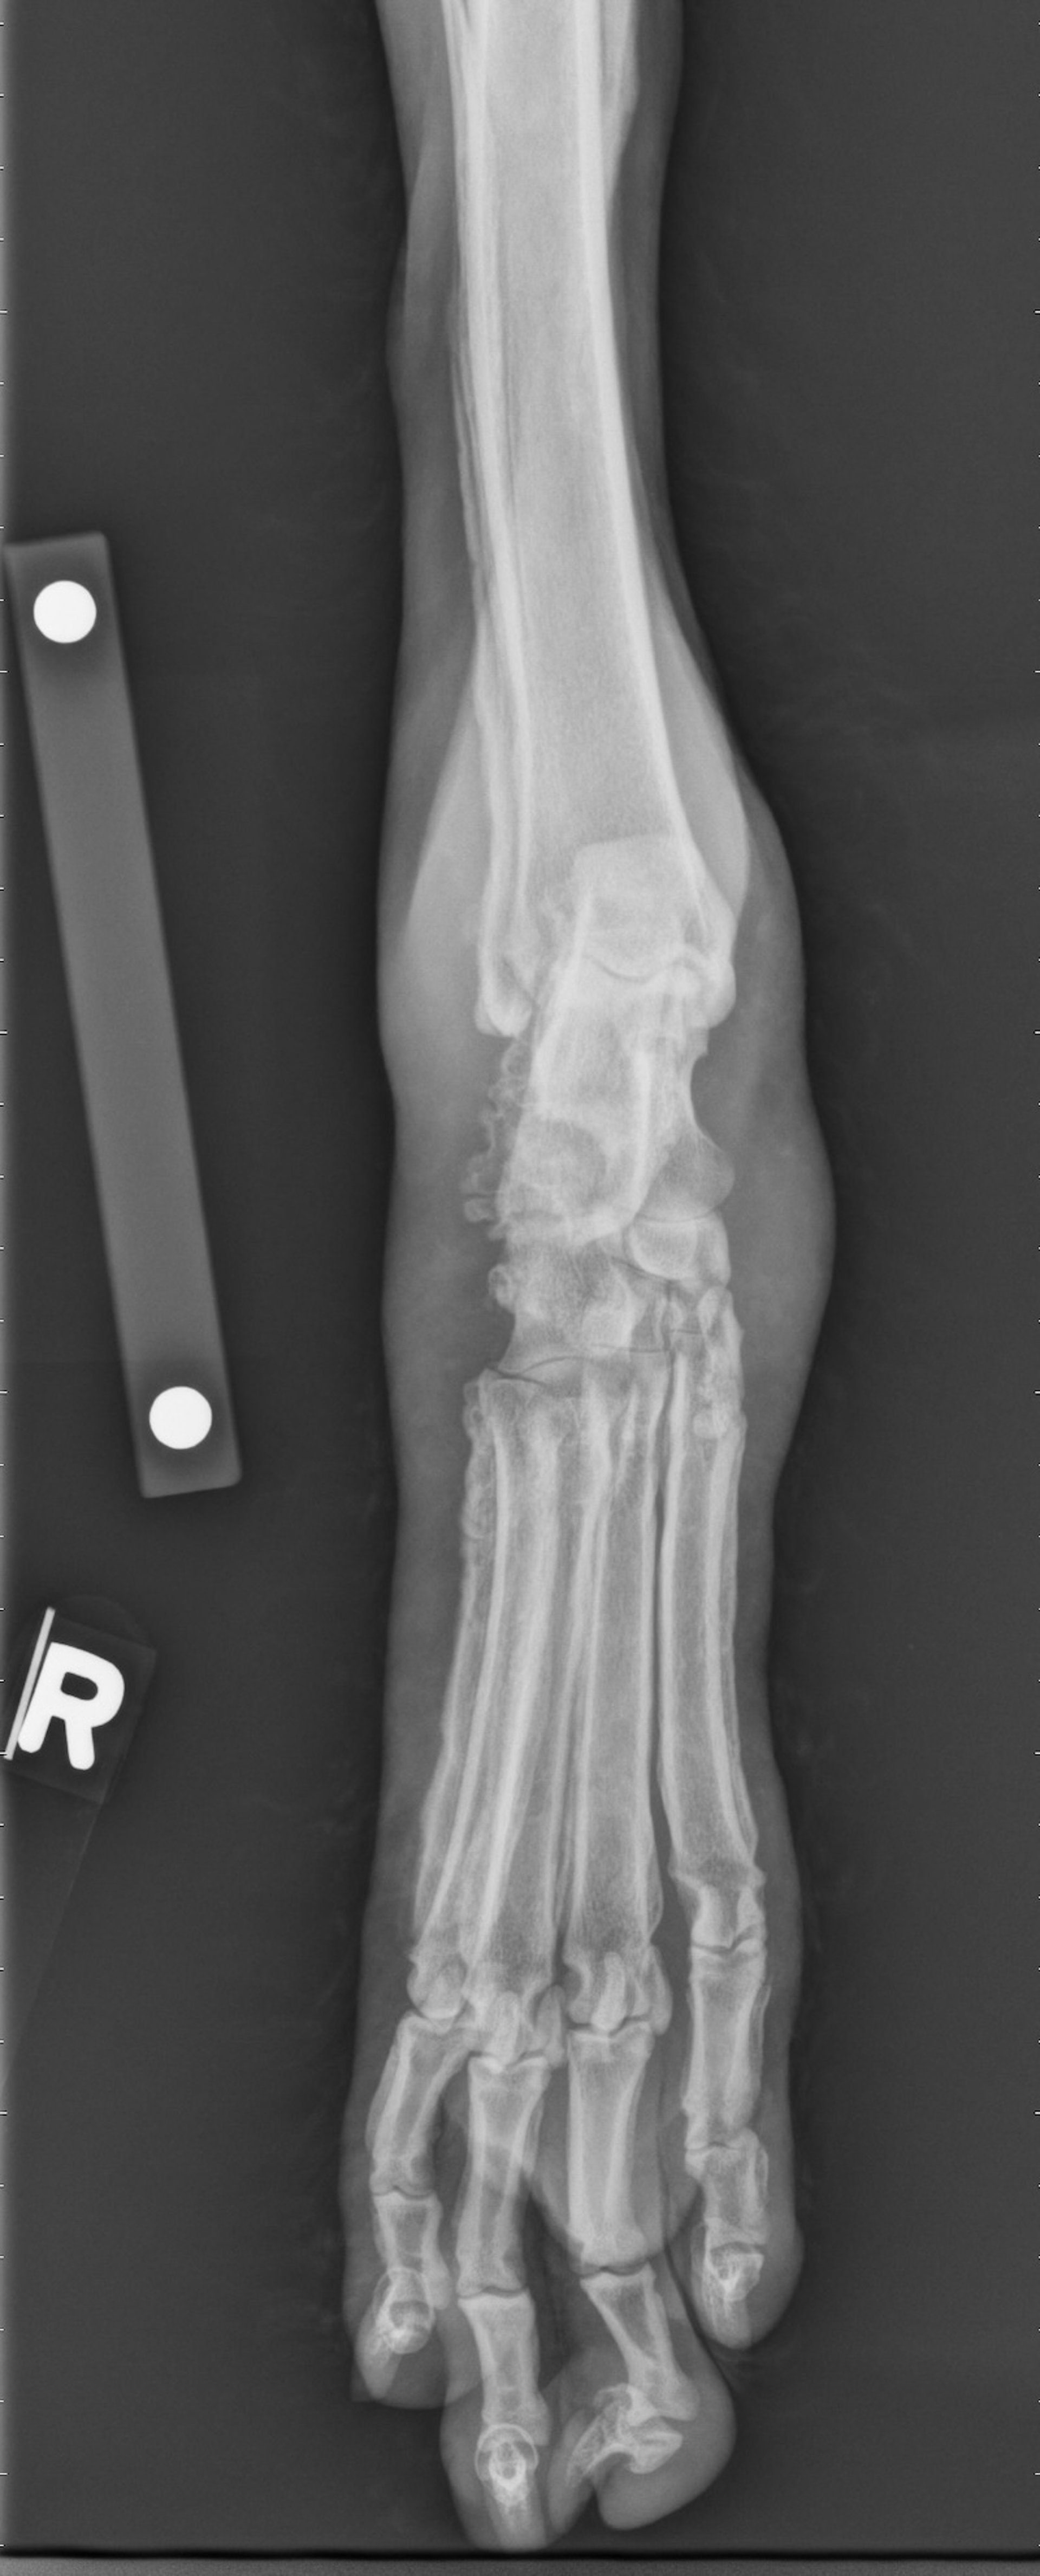

Hypertrophic osteopathy, radiograph, dog